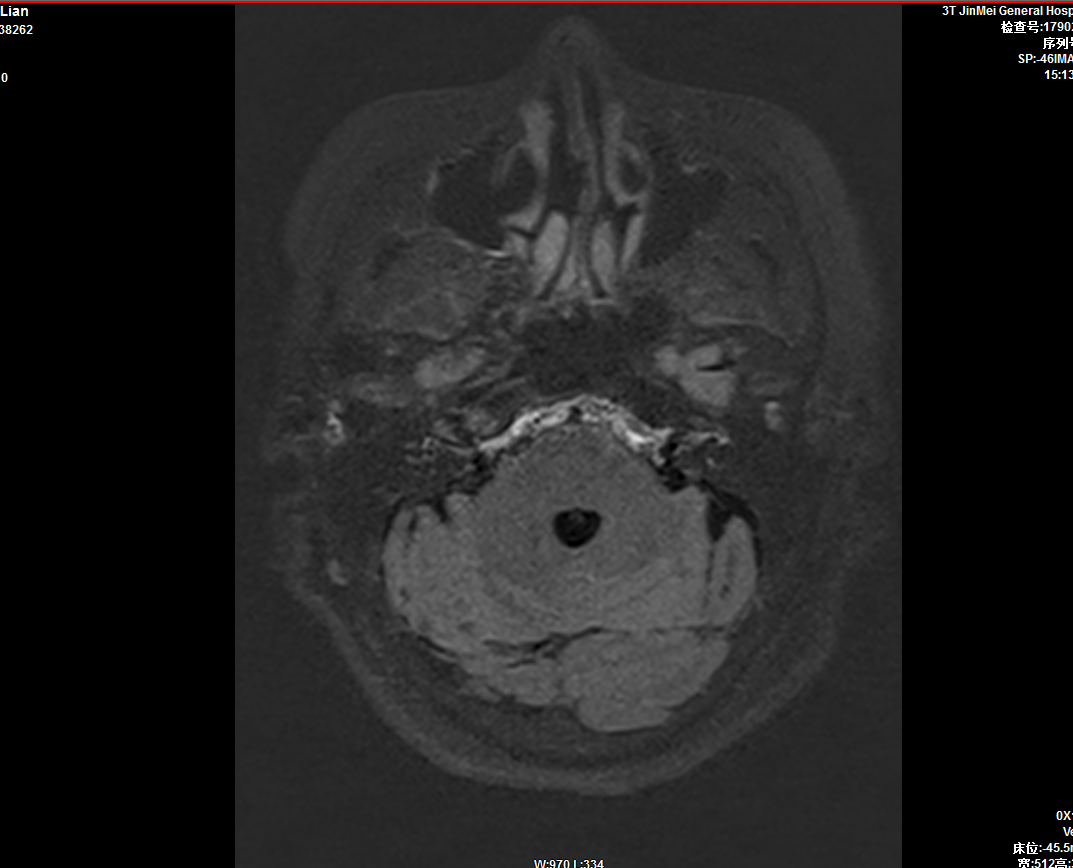

內(nèi)耳釓造影

5、是目前公認(rèn)的唯一能夠活體顯示膜迷路積水的影像學(xué)檢查方法,在晉東南地區(qū)率先開(kāi)展,該技術(shù)大大提高了對(duì)膜迷路積水相關(guān)內(nèi)耳疾患的早診率,實(shí)現(xiàn)了精準(zhǔn)診斷、早期干預(yù)、規(guī)范治療。